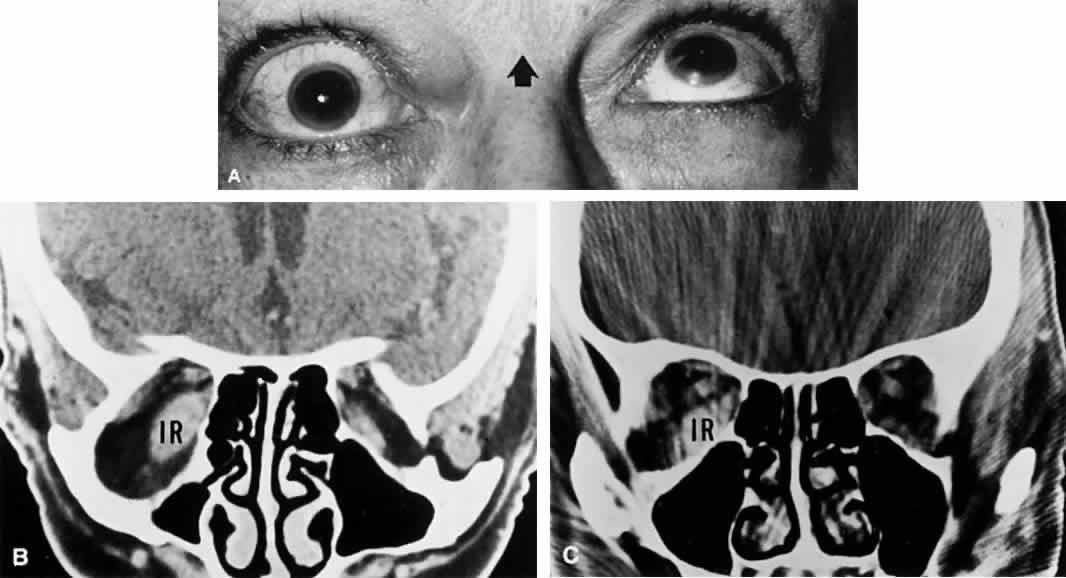

Before entering the cavernous sinus, the abducens nerve lies in relationship to the medial aspect of the petrous bone. Inflammation of the petrous bone and its dura may occur secondary to middle-ear infections, with involvement of the facial nerve (facial palsy), the trigeminal ganglion (pain in the eye or face), and the abducens nerve (lateral rectus palsy). These signs and symptoms constitute the now rare Gradenigo syndrome. The combination of sixth and seventh nerve palsies, even bilateral, is not uncommon in closed-head trauma, especially when the skull is compressed in its horizontal diameter (Fig. 6); this results in transverse fractures of the temporal bone. Leakage of blood or spinal fluid from the external ear canal, hemotympanum, or mastoid ecchymosis (Battle's sign) may be further evidence of basal fracture.

Fig. 6. Bilateral sixth and seventh nerve palsies due to basal skull fracture. A. Left gaze. B. Right gaze. C. Attempted lid closure demonstrates intact Bell's phenomenon and lagophthalmos.